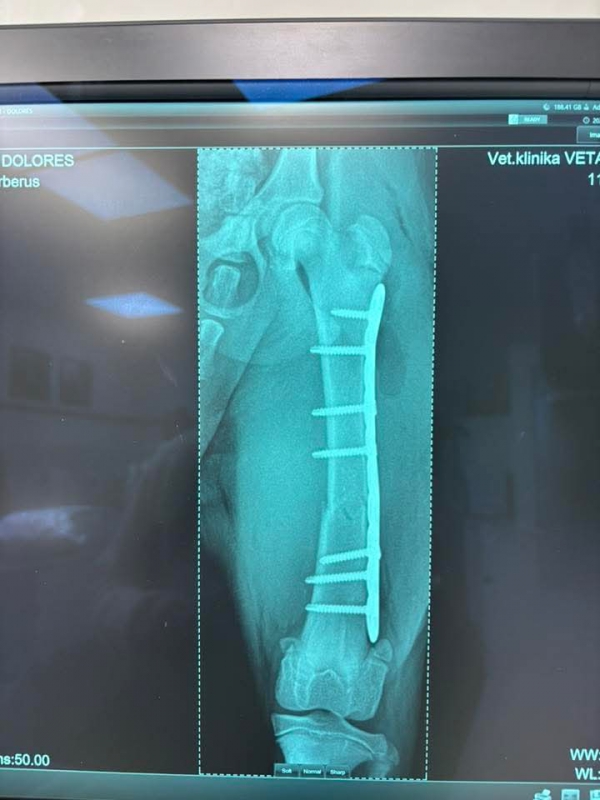

DOLORES má po operácii ♥. Ďakujeme všetkým za pomoc ♥♥♥. Držte malej palce aby bola čoskoro fit :)

Dolores po operácii pozdravuje. Zotavuje sa výborne a rýchlejšie ako sme mysleli ♥♥♥